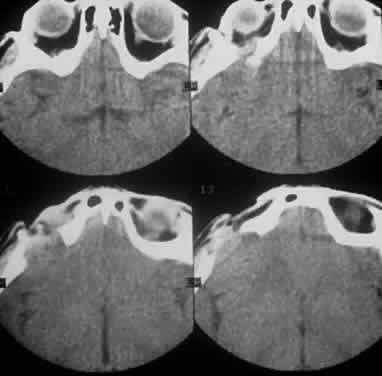

Computed tomography (CT) accurately demonstrates the molding of the mass to orbital structures, such as the globe and orbital bones, without bony erosion except in large cell lymphoma (Fig. 7). CT is used to localize the lesion, which tends to be unilateral and in both the intraconal and extraconal spaces. Lesions limited to the conjunctiva tend to be more benign with a better long-term prognosis, whereas those that extend into the orbit tend to be more malignant. Conjunctival lesions remain localized in 90% of cases, whereas orbital and lid lesions have a higher rate of systemic extranodal involvement.63 Lymphoid lesions of the lacrimal gland appear as a diffuse vertical expansion of the gland, which mold to both the globe and orbital bone without producing a bony fossa or erosion64 (Fig. 8). If the lesion extends beyond the orbital rim, the palpebral lobe of the gland is involved, and posterior or orbital lobe involvement appears as a straight line against orbital fat. Pleomorphic adenoma, on the other hand, appears as an oval, globular lesion with, in 80% of cases, adjacent bone changes caused by the firmer stroma of the tumor. Because epithelial tumors usually arise in the orbital lobe, extension beyond the orbital rim is not a feature.65 CT scan cannot distinguish between inflammatory and lymphoid lesions, because both lesions are homogeneous and enhance with intravenous contrast, and at biopsy, orbital lymphoid lesions are pink with a friable texture caused by the absence of stroma.66–68 The subtype and malignancy of the lesion can only be determined morphologically. The following subtypes of B-cell nonHodgkin's malignant lymphoma—extranodal B-cell marginal zone lymphoma, follicle center cell lymphoma, small lymphocytic lymphoma, lymphoplasmacytoid lymphoma, mantle cell lymphoma, large cell lymphoma, and Burkitt's lymphoma—are discussed in the approximate order of frequency with which they occur in the orbit.

Fig. 7. A CT scan, axial view, of the patient in Figure 6 showing molding of the lymphoma to adjacent extraocular muscle, globe, and medial orbital wall.

Fig. 8. A CT scan, axial view, of a B-cell lymphoma localized to the anterior orbit bilaterally, with left lacrimal gland involvement and a normal adjacent lateral wall.